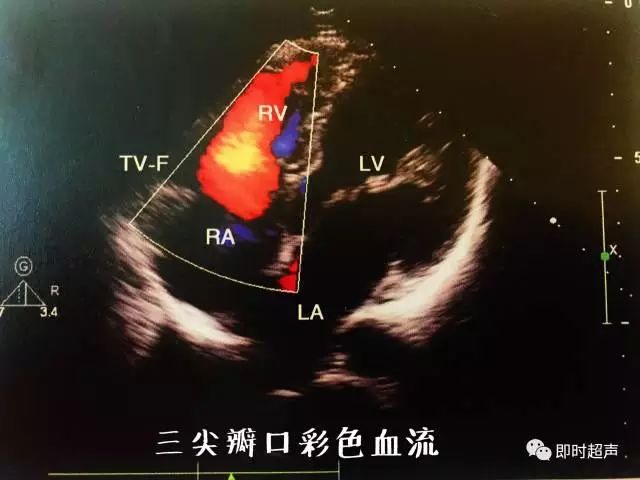

十二、彩色多普勒血流成像